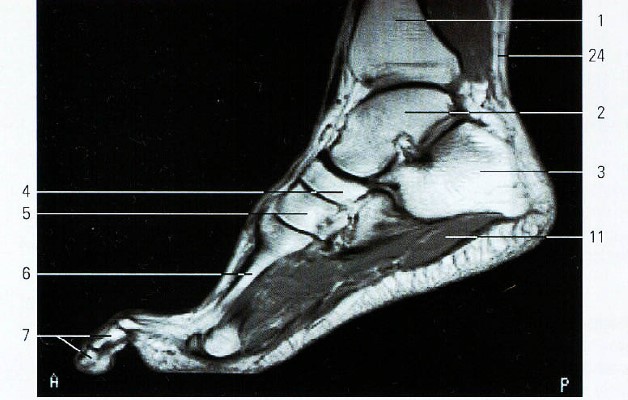

Артроз диагностируют при помощи рентгенологического исследования. Однако, заболевание первой степени не всегда видно на снимках, поэтому врачи используют и другие современные и более точные методы:

- компьютерную томографию;

- МРТ.

Пациенту также придется сдать анализ крови, чтобы исключить артрит. Ниже на фото представлен артроз первой степени и последующие стадии развития заболевания.